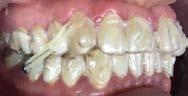

Paciente de 14 años y 8 meses, moti vo de consulta: “mi mordida no me gusta” el patrón esquelético es cla se II, hiperdivergente, clase II molar derecha y clase I molar izquierda, los caninos superiores en infraoclusión overbite disminuido, apiñamiento severo superior, moderado inferior, con los dientes 12 y 22 palatinizados, el 13 ectópico, con mordida abierta anterior, y las líneas medias desvia das.

Estudios de inicio fotografías intrao rales en la de frente se ven la línea media dental superior esta desviada

hacia la derecha y la línea media dental inferior a la izquierda, con mordida abierta anterior, el canino superior derecho se encuentra fuera del arco ( Figura 3 ), en la oclusal superior los inci sivos laterales palatini zados y paladar ojival profundo, en la lateral derecha una relación molar clase II y relación canina no determinable (Figura 4), en la izquier da una relación molar clase I y relación canina no deter minada.

172. Diciembre 2022 Corrección de mordida abierta anterior por deglución atípica Figura 3. Intraoral inicial de frente, la oclusal superior forma de arco triangular.